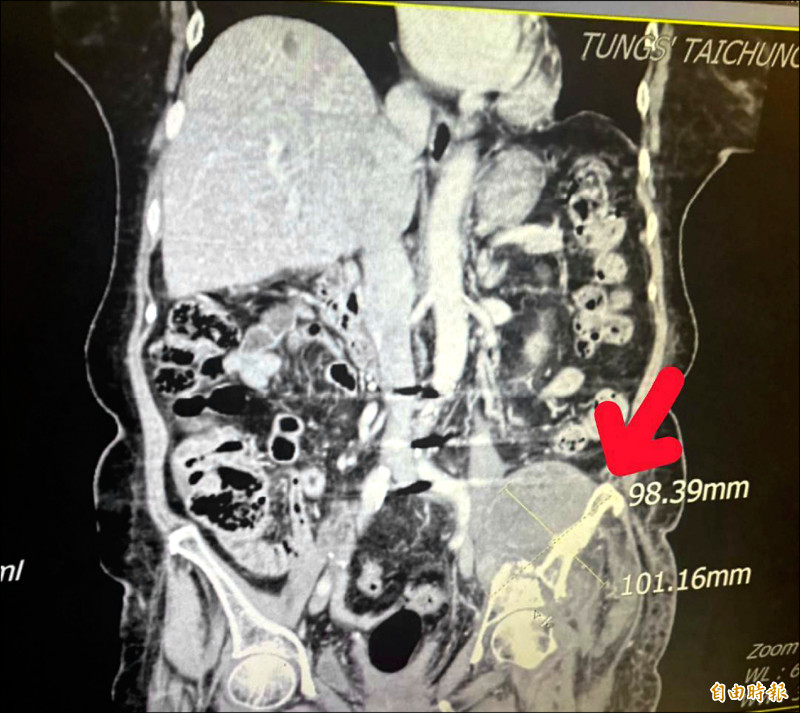

由於張婦的腫瘤細胞太大(約12.1公分×17.4公分),且腫瘤位置執行手術風險過高,葉啟源採用銳視刀適應性放射治療,利用空間分割點狀治療方式,局部給予點狀高劑量的放射線,以高劑量消融巨大、抗放射性腫瘤,再配合傳統銳視刀,即以傳統劑量梯度保護周圍的健康組織與器官,經過1個月26次治療後,腫瘤縮小至9.8公分×10.1公分,緩解骶叢神經受壓迫的情況,患者疼痛及行動能力明顯改善。